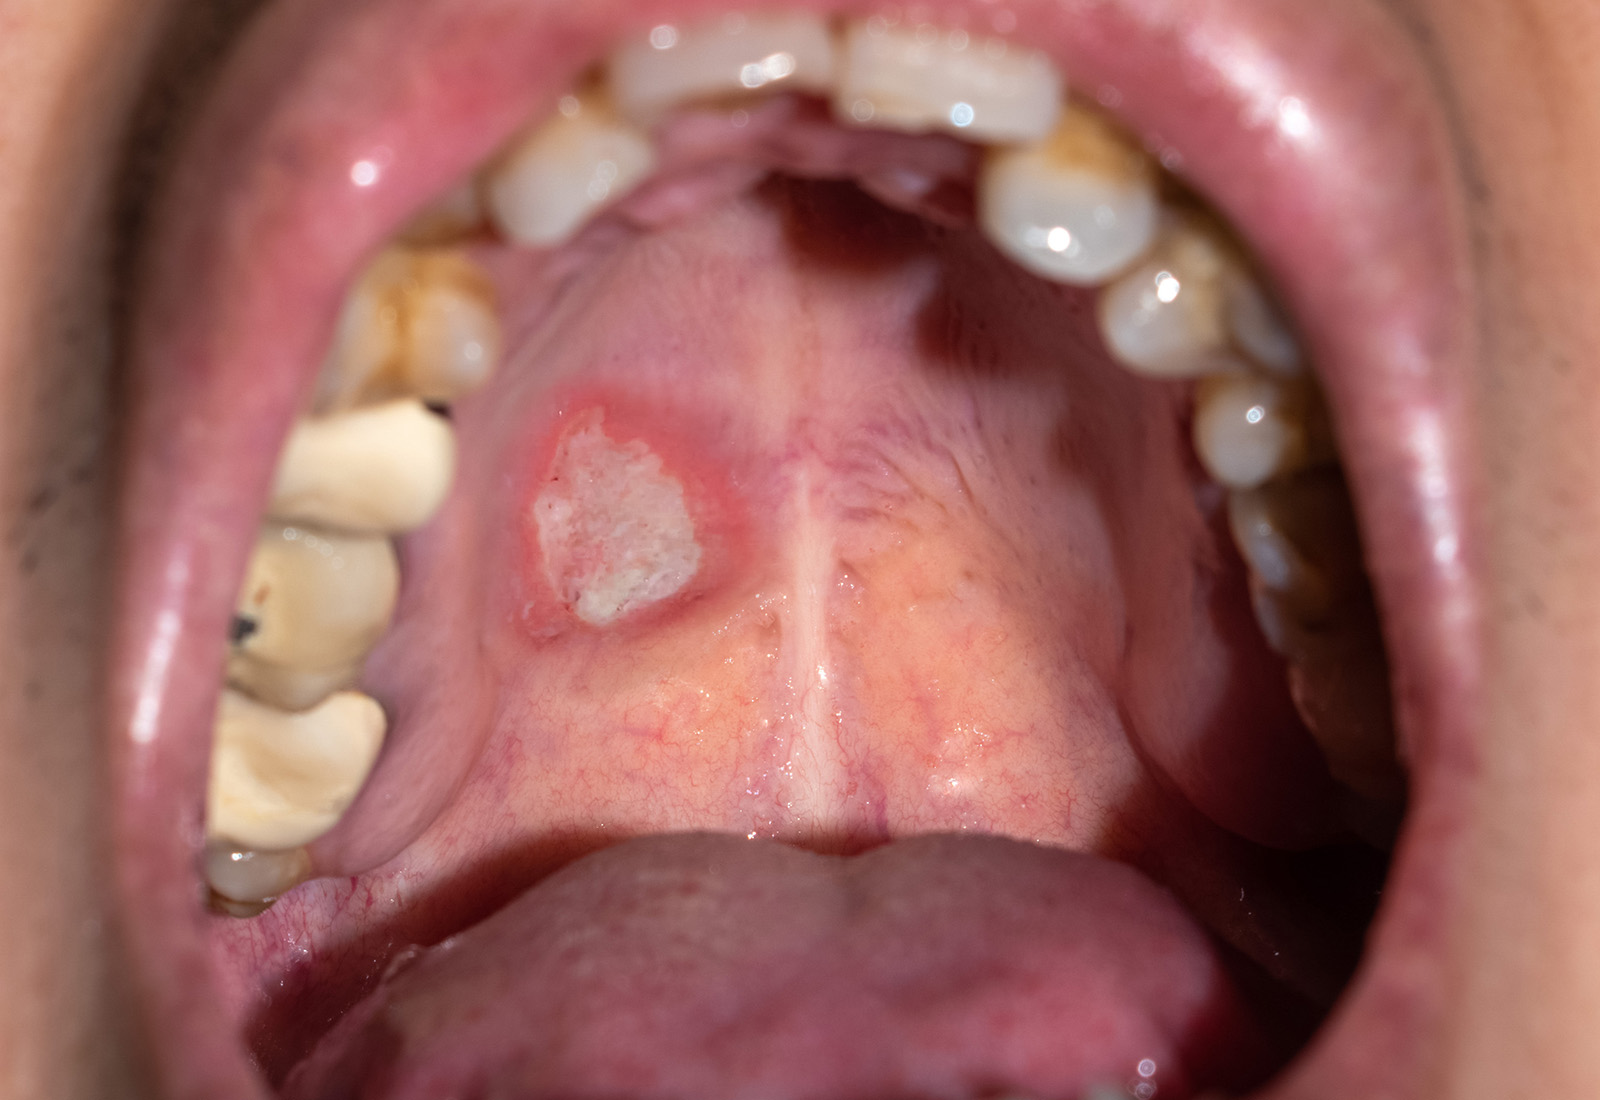

Kanker mulut adalah pertumbuhan sel abnormal pada sel epitel yang berada dalam rongga mulut, sehingga terjadinya pertumbuhan sel yang tidak terkendali. Beberapa bagian dalam mulut yang bisa mengalami kanker antara lain, kanker bibir, kanker lidah, kanker gusi, kanker pipi bagian dalam, kanker langit-langit mulut, dan kanker dasar lidah.

Sering kali, gejala kanker mulut pada tahap awal sulit dikenali, karena hampir sama dengan penyakit mulut lainnya. Misalnya, Anda bisa saja menemukan adanya sariawan atau bercak putih yang tidak bisa dihilangkan dan terjadi untuk waktu yang lama.

Kanker mulut bisa terjadi di bibir, lidah, gusi, pipi bagian dalam, langit-langit mulut, hingga dasar mulut. Area yang terkena kanker mulut mungkin menunjukkan tanda seperti bercak merah atau putih, benjolan, atau luka yang sulit sembuh.